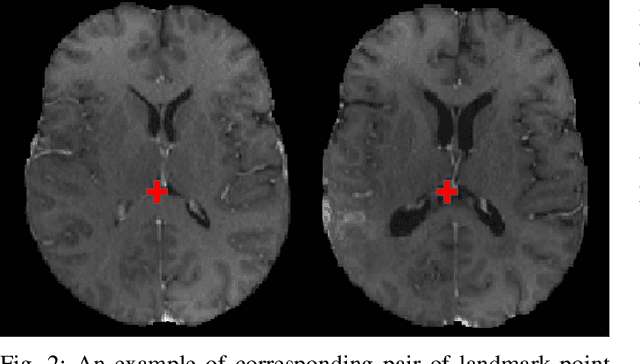

Abstract:Registration of longitudinal brain Magnetic Resonance Imaging (MRI) scans containing pathologies is challenging due to tissue appearance changes, and still an unsolved problem. This paper describes the first Brain Tumor Sequence Registration (BraTS-Reg) challenge, focusing on estimating correspondences between pre-operative and follow-up scans of the same patient diagnosed with a brain diffuse glioma. The BraTS-Reg challenge intends to establish a public benchmark environment for deformable registration algorithms. The associated dataset comprises de-identified multi-institutional multi-parametric MRI (mpMRI) data, curated for each scan's size and resolution, according to a common anatomical template. Clinical experts have generated extensive annotations of landmarks points within the scans, descriptive of distinct anatomical locations across the temporal domain. The training data along with these ground truth annotations will be released to participants to design and develop their registration algorithms, whereas the annotations for the validation and the testing data will be withheld by the organizers and used to evaluate the containerized algorithms of the participants. Each submitted algorithm will be quantitatively evaluated using several metrics, such as the Median Absolute Error (MAE), Robustness, and the Jacobian determinant.